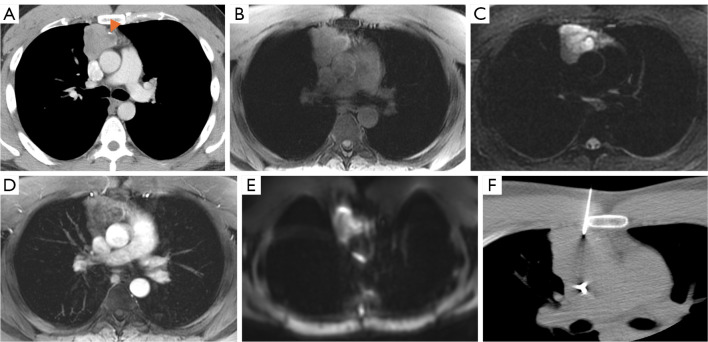

Abstract Image